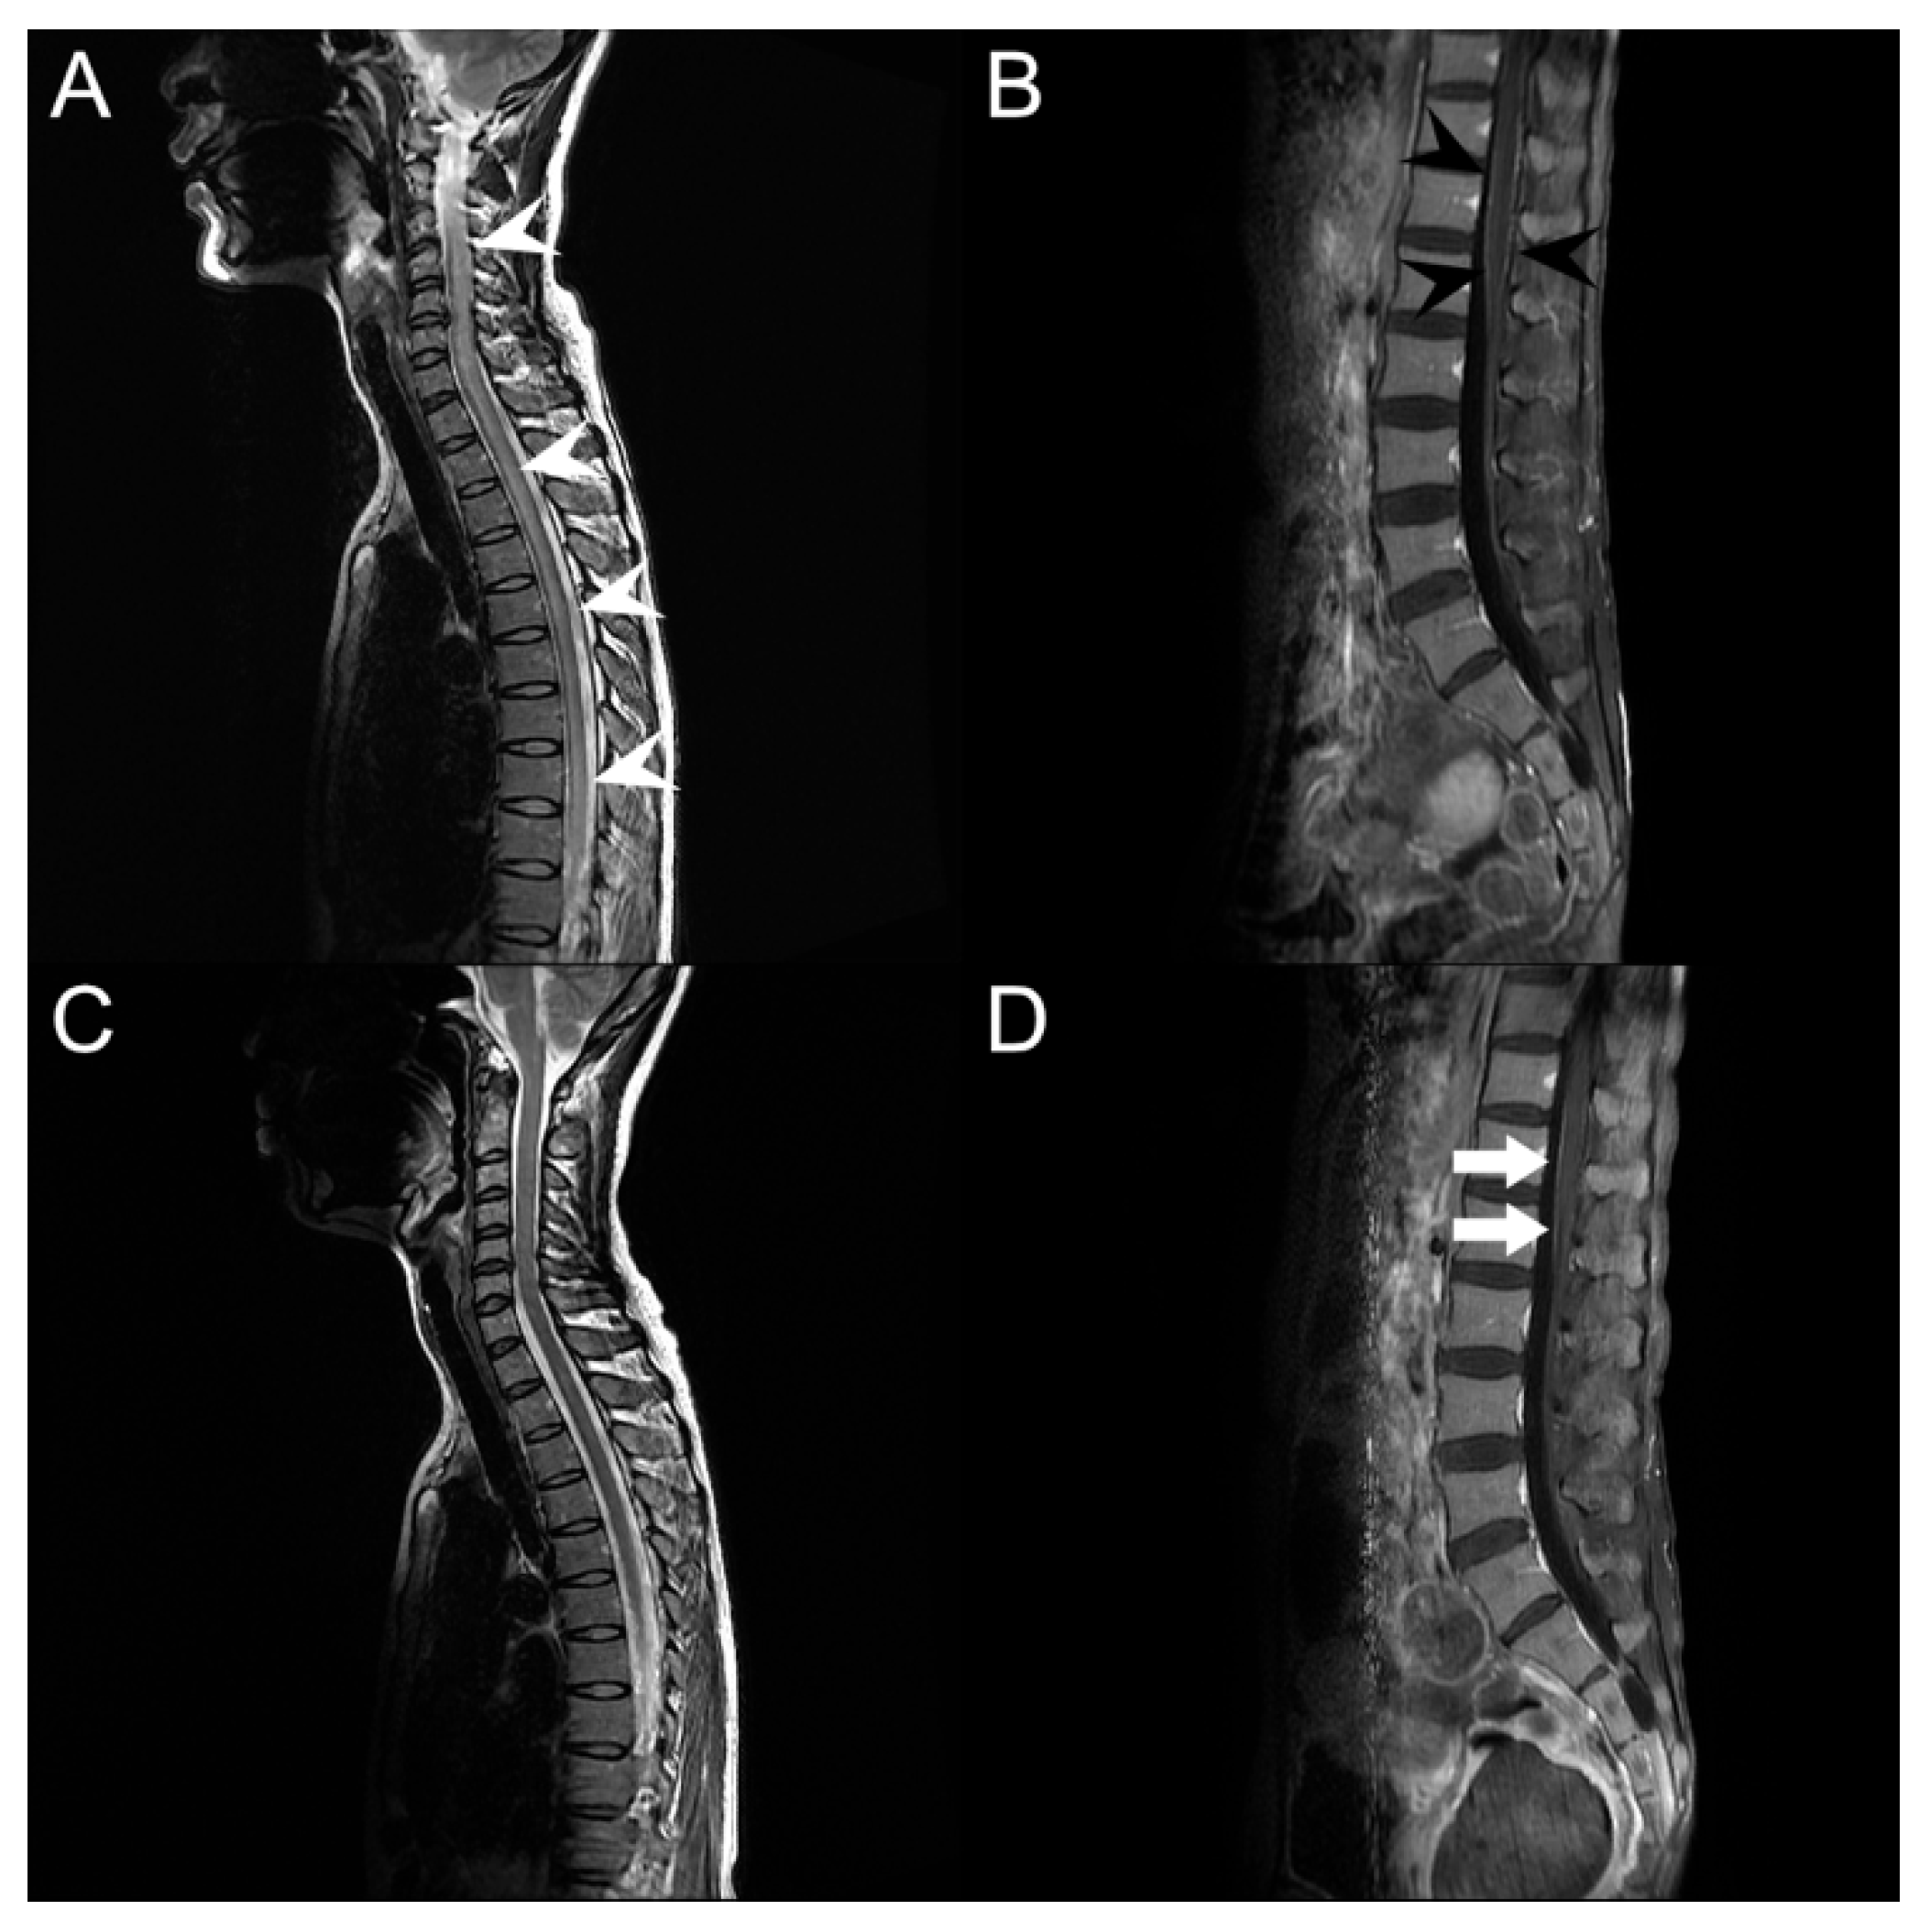

Routine blood tests performed on the day of admission showed an elevated C-reactive protein (CRP) level (7.09; normal range < 0.5) and erythrocyte sedimentation rate (74 mm/h; normal range 0–20 mm/h). Venereal disease research laboratory (VDRL) test, human immunodeficiency virus (HIV) antigen, and antibody tests were negative. Other laboratory results, including vitamins B1, B6, B12, methylmalonic acid, thyroid-stimulating hormone, T3, hemoglobin A1c, Jo-1, SS-A/Ro, SS-B/La, double-stranded DNA, paraneoplastic antibodies, and anti-ganglioside antibodies, were within the normal range. The opening pressure of the lumbar puncture for CSF analysis was 11 cmH2O with a clear color. However, CSF testing showed polymorphonuclear dominant (73.6%) pleocytosis (total white blood cell count 602/µL; normal range 0–5/µL) with elevated levels of protein (188.4 mg/dL; normal range 15–45 mg/dL). The CSF VDRL test results were also negative. The IgG index increased slightly to 0.98, with a negative oligoclonal band. Other specific infection markers, including CMV, Mycobacterium tuberculosis, Mycoplasma pneumoniae, varicella-zoster virus, herpes simplex virus type I and II, Streptococcus pneumoniae, Neisseria meningitidis, Hemophilus influenzae type 1, Listeria monocytogenes, Group B streptococcus, and Cryptococcus, were negative in the CSF. Serum and urine immunofixation did not reveal any abnormal bands. The PCR test for SARS-CoV-2 in the CSF was negative. No pathogenic bacteria were cultured from the blood, urine, sputum, or CSF. The results of the nerve conduction study (NCS) were normal. Magnetic resonance imaging (MRI) revealed a high signal intensity in the intramedullary spinal cord from C1 to the conus medullaris on a T2-weighted image (Figure 2A). The signal was also highlighted in the T11 to L2 level pia mater on an enhanced T1-weighted image (Figure 2B). However, diffusion-weighted imaging (DWI) did not reveal any abnormal signal changes. These findings led us to suspect immune-triggered transverse myelitis and infectious polyradiculitis. We started administering intravenous steroid (methylprednisolone 1 g daily) for five days and an antiviral agent (acyclovir 30 mg/kg daily) and antibiotics (ceftriaxone 4 g and vancomycin 2 g daily) for 14 days (Figure 1) to the patient.

Seven days after starting medication, the bilateral leg weakness began to improve to grade 4, and the knee jerk was 1+ with a positive Babinski sign on the left. Sensory disturbance improved bilaterally below the T7 level. In the follow-up evaluation, NCS identified prolonged gastrocnemius-soleus H-reflexes, and needle electromyography (EMG) showed positive sharp waves on the thoracic and lumbosacral paraspinal muscles, which indicated polyradiculopathy. Follow-up blood and CSF tests revealed remarkable improvement. The serum CRP level returned to the normal range without leukocytosis, and the WBC count and protein level in the CSF were normal at 4/µL and 33.1 mg/dL, respectively. The follow-up infection markers, including PCR for SARS-CoV-2 in the CSF, were still negative. There was no noticeable growth in the blood, CSF, urine, or sputum cultures. Moreover, MRI revealed a normal T2-weighted signal intensity in the spinal cord (Figure 2C). Nevertheless, the enhancement of the pia mater located at the conus medullaris remained (Figure 2D). Two months after admission, the patient’s overall neurological manifestations recovered. Motor weakness improved to 5 in the MRC grading system, except for the bilateral proximal leg, which was graded as 4+, which allowed her to ambulate without assistance. The sensory level decreased from T7 to L1, and the DTR returned to normal. However, the patient still complained of mild voiding difficulties and constipation.

Infectious polyradiculitis is common in patients with acquired immunodeficiency syndrome, with CMV being the most common opportunistic pathogen [13]. CSF analysis findings of CMV polyradiculitis include polymorphonuclear pleocytosis and an elevated protein level, resembling bacterial meningitis [13]. Although CSF PCR results for HIV, CMV, and SARS-CoV-2 were negative in our patient, the elevated protein level and polymorphonuclear pleocytosis in CSF were similar to those previously reported, which supports the diagnosis of viral polyradiculitis in our patient [13]. The enhancement of the pia mater on the conus medullaris on T1-weighted sagittal gadolinium-enhanced imaging also supported the diagnosis of infectious polyradiculitis (Figure 2C,D).

Figure 2. Spine magnetic resonance imaging. (A) T2-weighted sagittal imaging on admission shows abnormal intramedullary hyperintensity lesions from C1/2 to conus medullaris (white arrowheads). (B) T1-weighted sagittal gadolinium-enhanced imaging shows enhancement of pia mater on the conus medullaris (black arrowheads). (C) Intramedullary hyperintensity is improved after treatment. (D) Enhancement of pia mater remains even after treatment (white arrows).